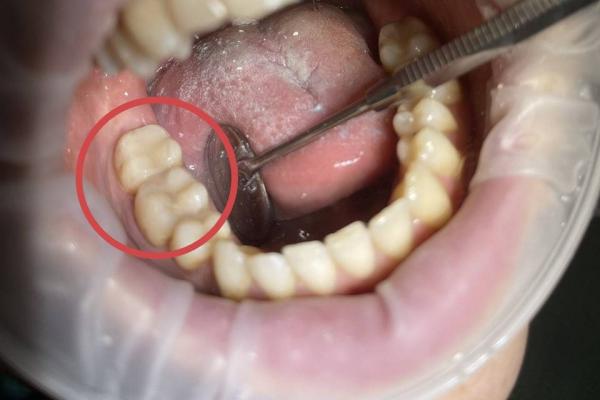

Профессиональная гигиена с использованием ультразвука включает в себя: - удаление твердых зубных отложений с помощью ультразвукового скейлера - полировка зубов профессиональной щеткой и пастой "Kerr super polish" - покрытие зубов фторосодержащим препаратом - метод рекомендован для удаления зубного камня |